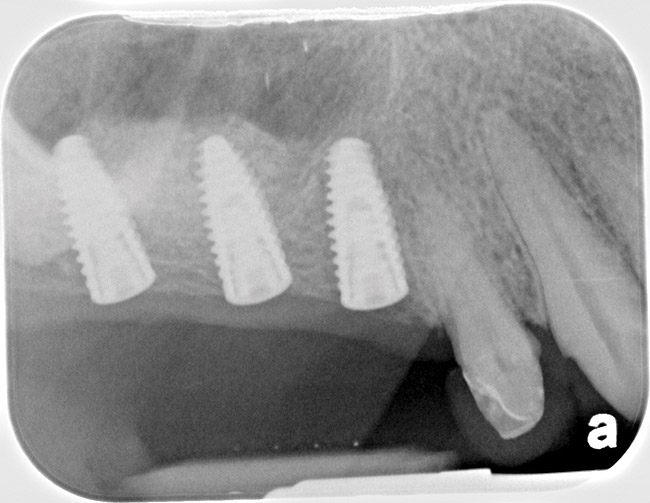

Fig 14. Peri-apical X-ray of the site immediately following sinus floor elevation and implant insertion.

Figure 14

Fig 15. Peri-apical X-ray 5 months following the procedure. Notice bone mantel over the implants.

Figure 15